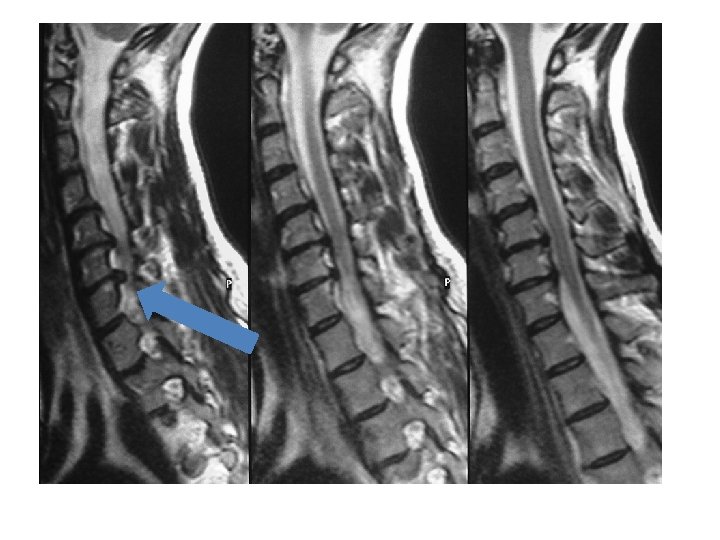

IRM en T 2 coupes sagittales

IRM en T 2 coupes axiales

Cas clinique 1 • Examens complémentaires: – EMG résultat: atteinte neurogène C 7 gauche – Analyse de l’IRM: discopathies multiples , déshydratation des disques, déformation rachidienne, conflit disco radiculaire foraminal C 7 gauche • Propositions de prise en charge?